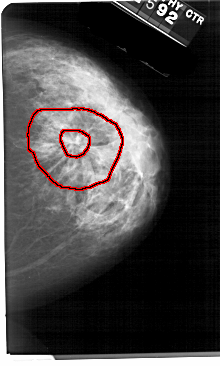

A_1693_1.RIGHT_CC

FILE: A_1693_1.RIGHT_CC.OVERLAY

TOTAL_ABNORMALITIES 1

ABNORMALITY 1

LESION_TYPE CALCIFICATION TYPE PLEOMORPHIC DISTRIBUTION CLUSTERED

LESION_TYPE MASS SHAPE IRREGULAR MARGINS SPICULATED

ASSESSMENT 5

SUBTLETY 4

PATHOLOGY MALIGNANT

TOTAL_OUTLINES 2

BOUNDARY

CORE